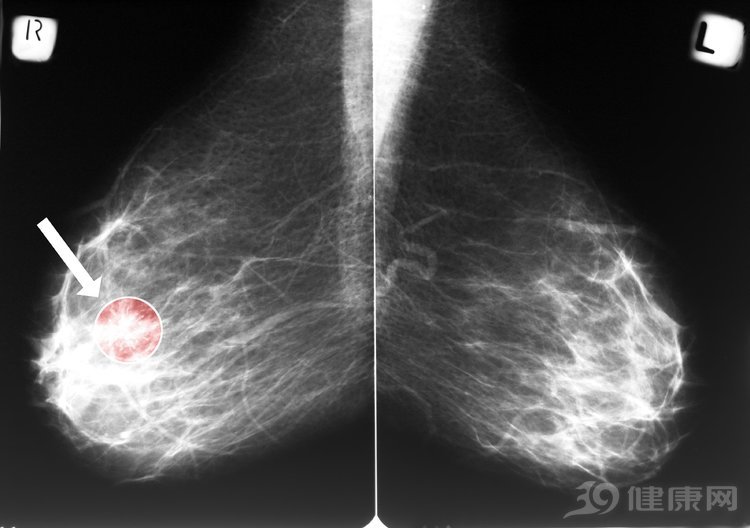

6、乳腺检查

近年来,乳腺癌已经严重威胁到女性的健康了,而乳腺癌如果能够及时发现的话,治愈率是很高的。现在乳腺癌的发病率已经向着低龄化发展了,因此女性的妇科检查中应该包含乳腺检查这一项。女性应该每年都做一次B超检查,而在35岁以后每年可以做一次钼靶。